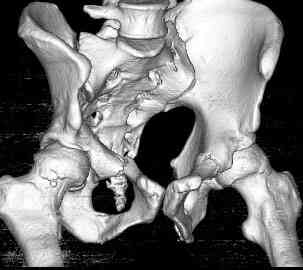

Уважаемые коллеги! опять вопрос по повреждению таза. Больной получил производственную травму 10 дней назад - удар балкой около 3 тонн в область верхней трети правого бедра и лона.

можно полечить в 2 этапа:как правило в области гребней гематомы все же не бывает, если гребни "свободны", то можно ограничиться на первом этапе передней рамой, вводя стержни через них (повреждение ротационно-нестабильное), затем после лечения отслаивающего повреждения Morel-Lavallee, выполнить открытую репозицию, внутреннюю фиксацию, возможно вместе с урологами. Тактику возможного лечения этой

Следующим этапом через 5-6 дней приступаем к фиксацию повреждения таза, иначе прооперериванные на фоне Morel-Lavallee повреждения осложняются инфицированием послеоперационной раны.

18.12. - отдельное спасибо еще раз А.В.Рункову- больного оперировали (А.В.Рунков) - произведен остеосинтез аппаратом - фиксация за крылья, два стержня в лонные кости и репозиция (почти полная) снимки будут чуть позже.

Дренировали отслойки на бедрах с их санацией. В правой ягодичной области сформировалась зона некроза. Больной "подвешен" за аппарат.